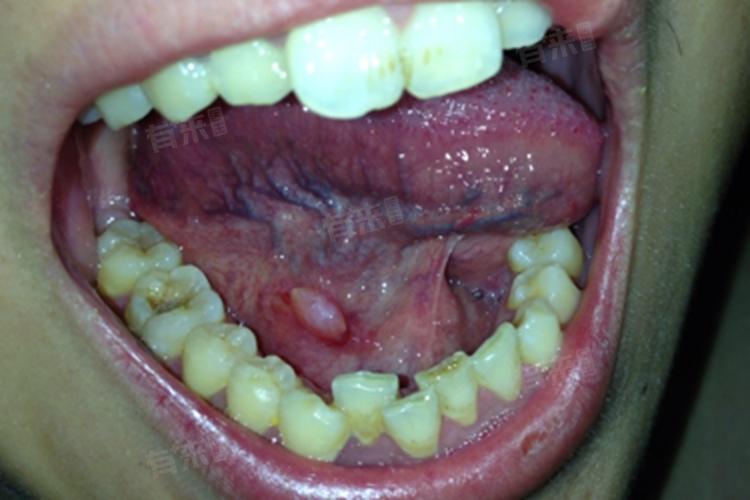

- 创伤性口腔溃疡:由于口腔内存在残根、残冠、不良修复体等尖锐物体,长期刺激口腔黏膜,导致溃疡形成。这种情况下,需要及时去除刺激因素,如拔除残根残冠、调磨尖锐牙尖等,保持口腔清洁,促进溃疡愈合。